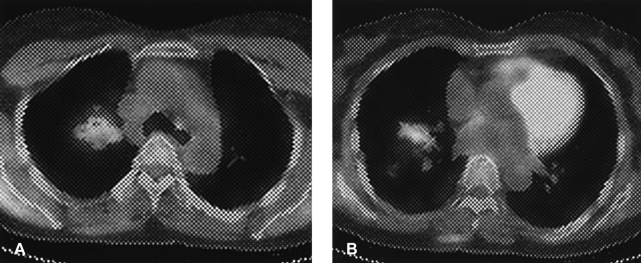

A 56-year-old woman presented with chest tightness, chronic cough and sputum that was present over the past three years. Her symptoms did not subside with medical treatment at local hospitals. The patient was referred to our hospital. The chest plain radiograph and chest CT scan showed multiple and relatively well-defined, multifocal peribronchiolar nodules (Figure 1). There were no contributory findings in the medical and social history.

Figure┬Ā1

Numerous parenchymal nodules in both upper lobe lung fields (A) and irregular thickening of the right major fissure (B).